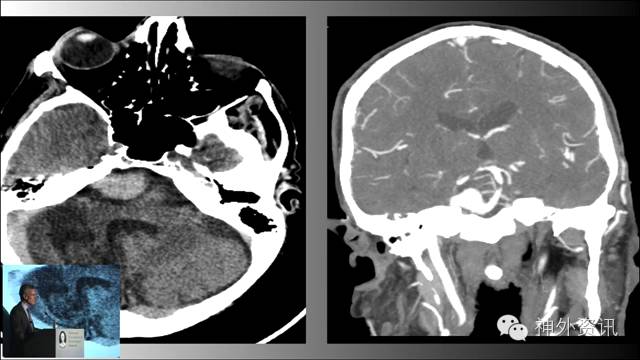

Michael T. Lawton,巴洛神经科学研究所(BNI)主席,精于各种脑血管疾病的治疗,已累及外科治疗4400余例颅内动脉瘤和700余例AVM,发表论文270余篇,参编书籍40余部,著有《Seven Aneurysms: Tenets and Techniques for Clipping》。